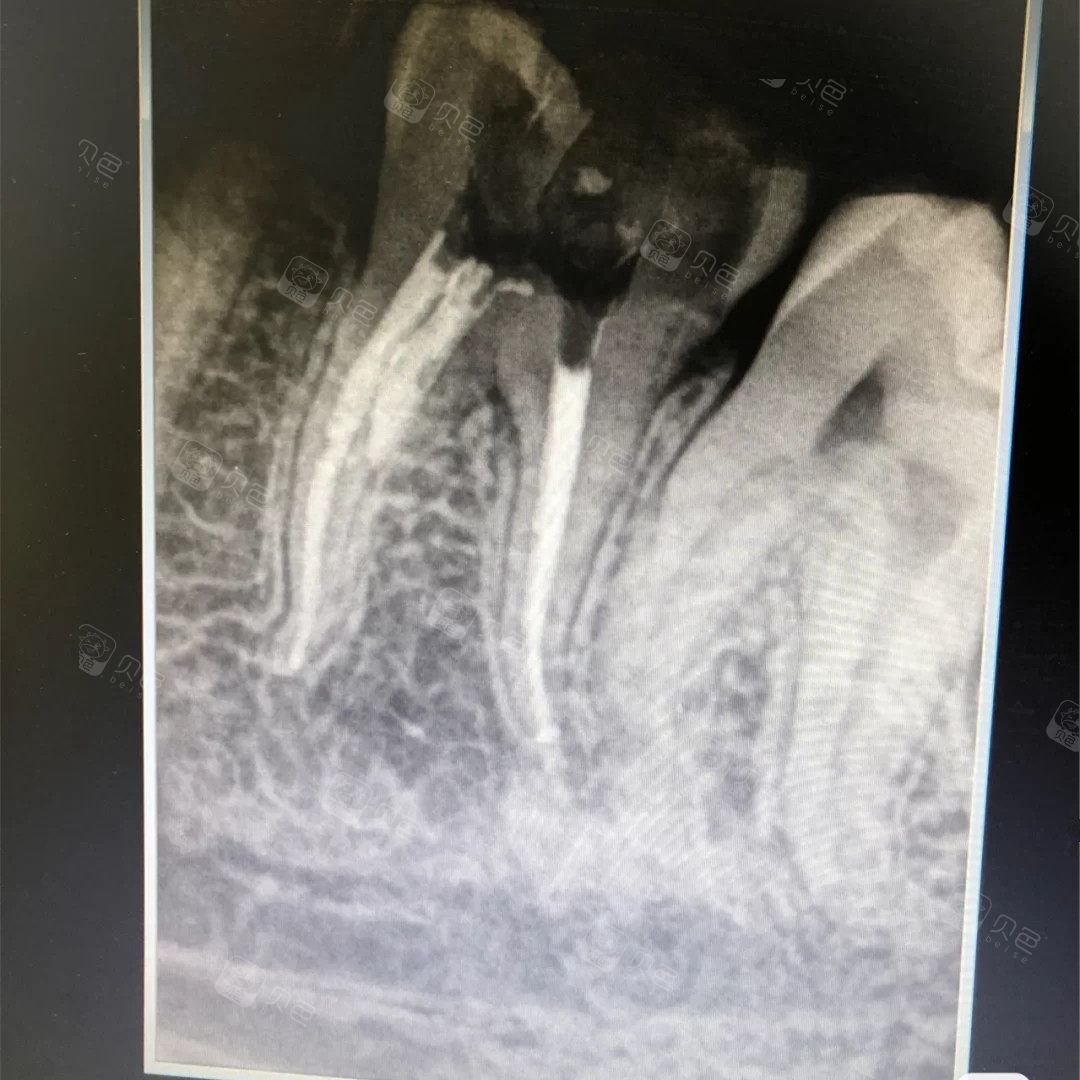

小牙片,小牙片伪影

蛀牙牙片

拍的牙片

小牙片怎么看